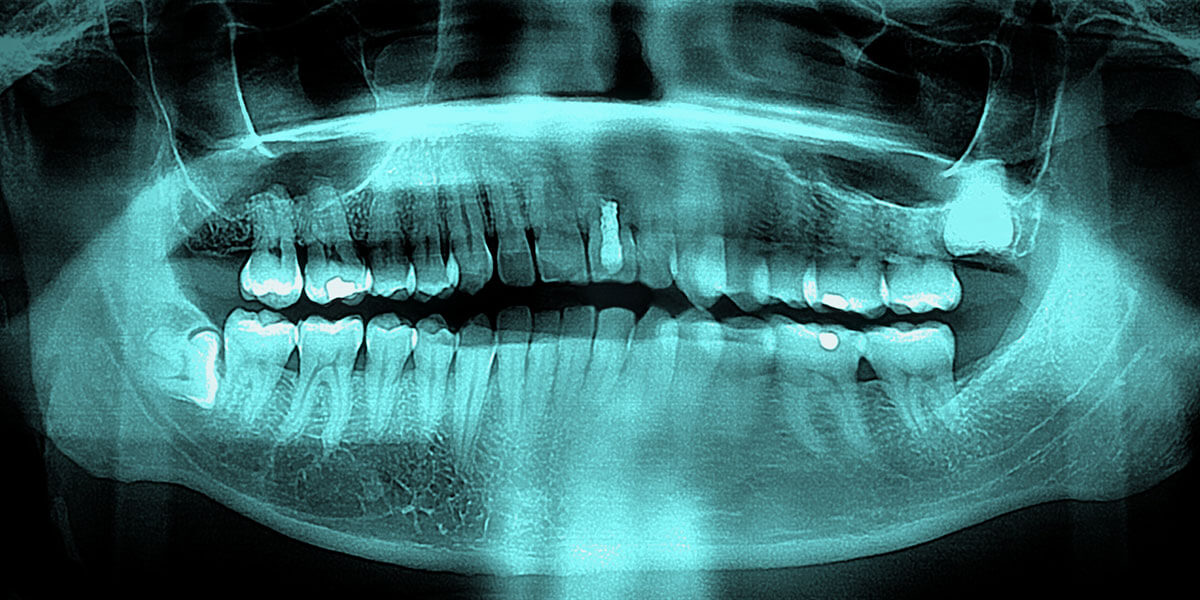

Digital X-ray

Digital x-rays reduce the amount of radiation needed as compared to film x-rays. The improved diagnostic capability of digital x-rays and the ability to view the x-rays on a computer screen allow the patient to better understand and follow treatment. Digital x-rays are instant, there is no longer a need to develop the film. Digital x-rays save time and increase patient care. It’s also a very green technology. By eliminating film, developer and chemical waste it is better for you and the environment!